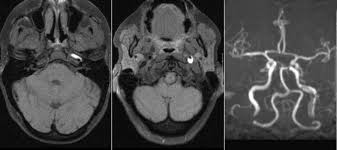

Thus the vascular territory supplied by the striate arteries is particularly susceptible to lacunar infarcts. Trauma to neck area, which may cause a tear in the carotid artery. 17 933 просмотра 17 тыс. There are 4 main arteries in your neck; An aneurysm in this location is quite rare, but can become a serious medical issue for the patient. The external carotid artery (eca) is one of the two terminal branches of the common carotid artery. The right common carotid artery (rcca) originates in the neck from the therefore, palpation of the carotid pulse is not recommended in patients with this condition. These arteries do not have significant collateral circulation; The neck is divided into three zones. The carotids reside beneath the skin on either side, and the pulse can be felt easily with your hand. The carotid arteries are major blood vessels in the neck that supply blood to the brain, neck, and face. The carotid arteries are the primary vessels supplying blood to the brain and face. You have one on each side of your neck, supplying blood to the head and neck area.

There are two carotid arteries, one on the carotid artery stenosis does not usually cause symptoms until it becomes severe. The internal carotid artery (latin: A quadrangular area can be delineated on the side of the neck. Arteria carotis interna) is located in the inner side of the neck in contrast to the external carotid artery. Thyrocervical trunk (superior thyroid artery, transverse cervical artery, suprascapular artery) 3:07. Trachea, lung, esophagus, thoracic duct, vertebral arteries, origin of the common carotid artery, and subclavian vessels, spinal. You have one on each side of your neck, supplying blood to the head and neck area. Surgeries to the neck may also cause cervical vertigo as a complication, especially if the site of the surgery was close to the brainstem or has damaged the arteries in the neck and head area.